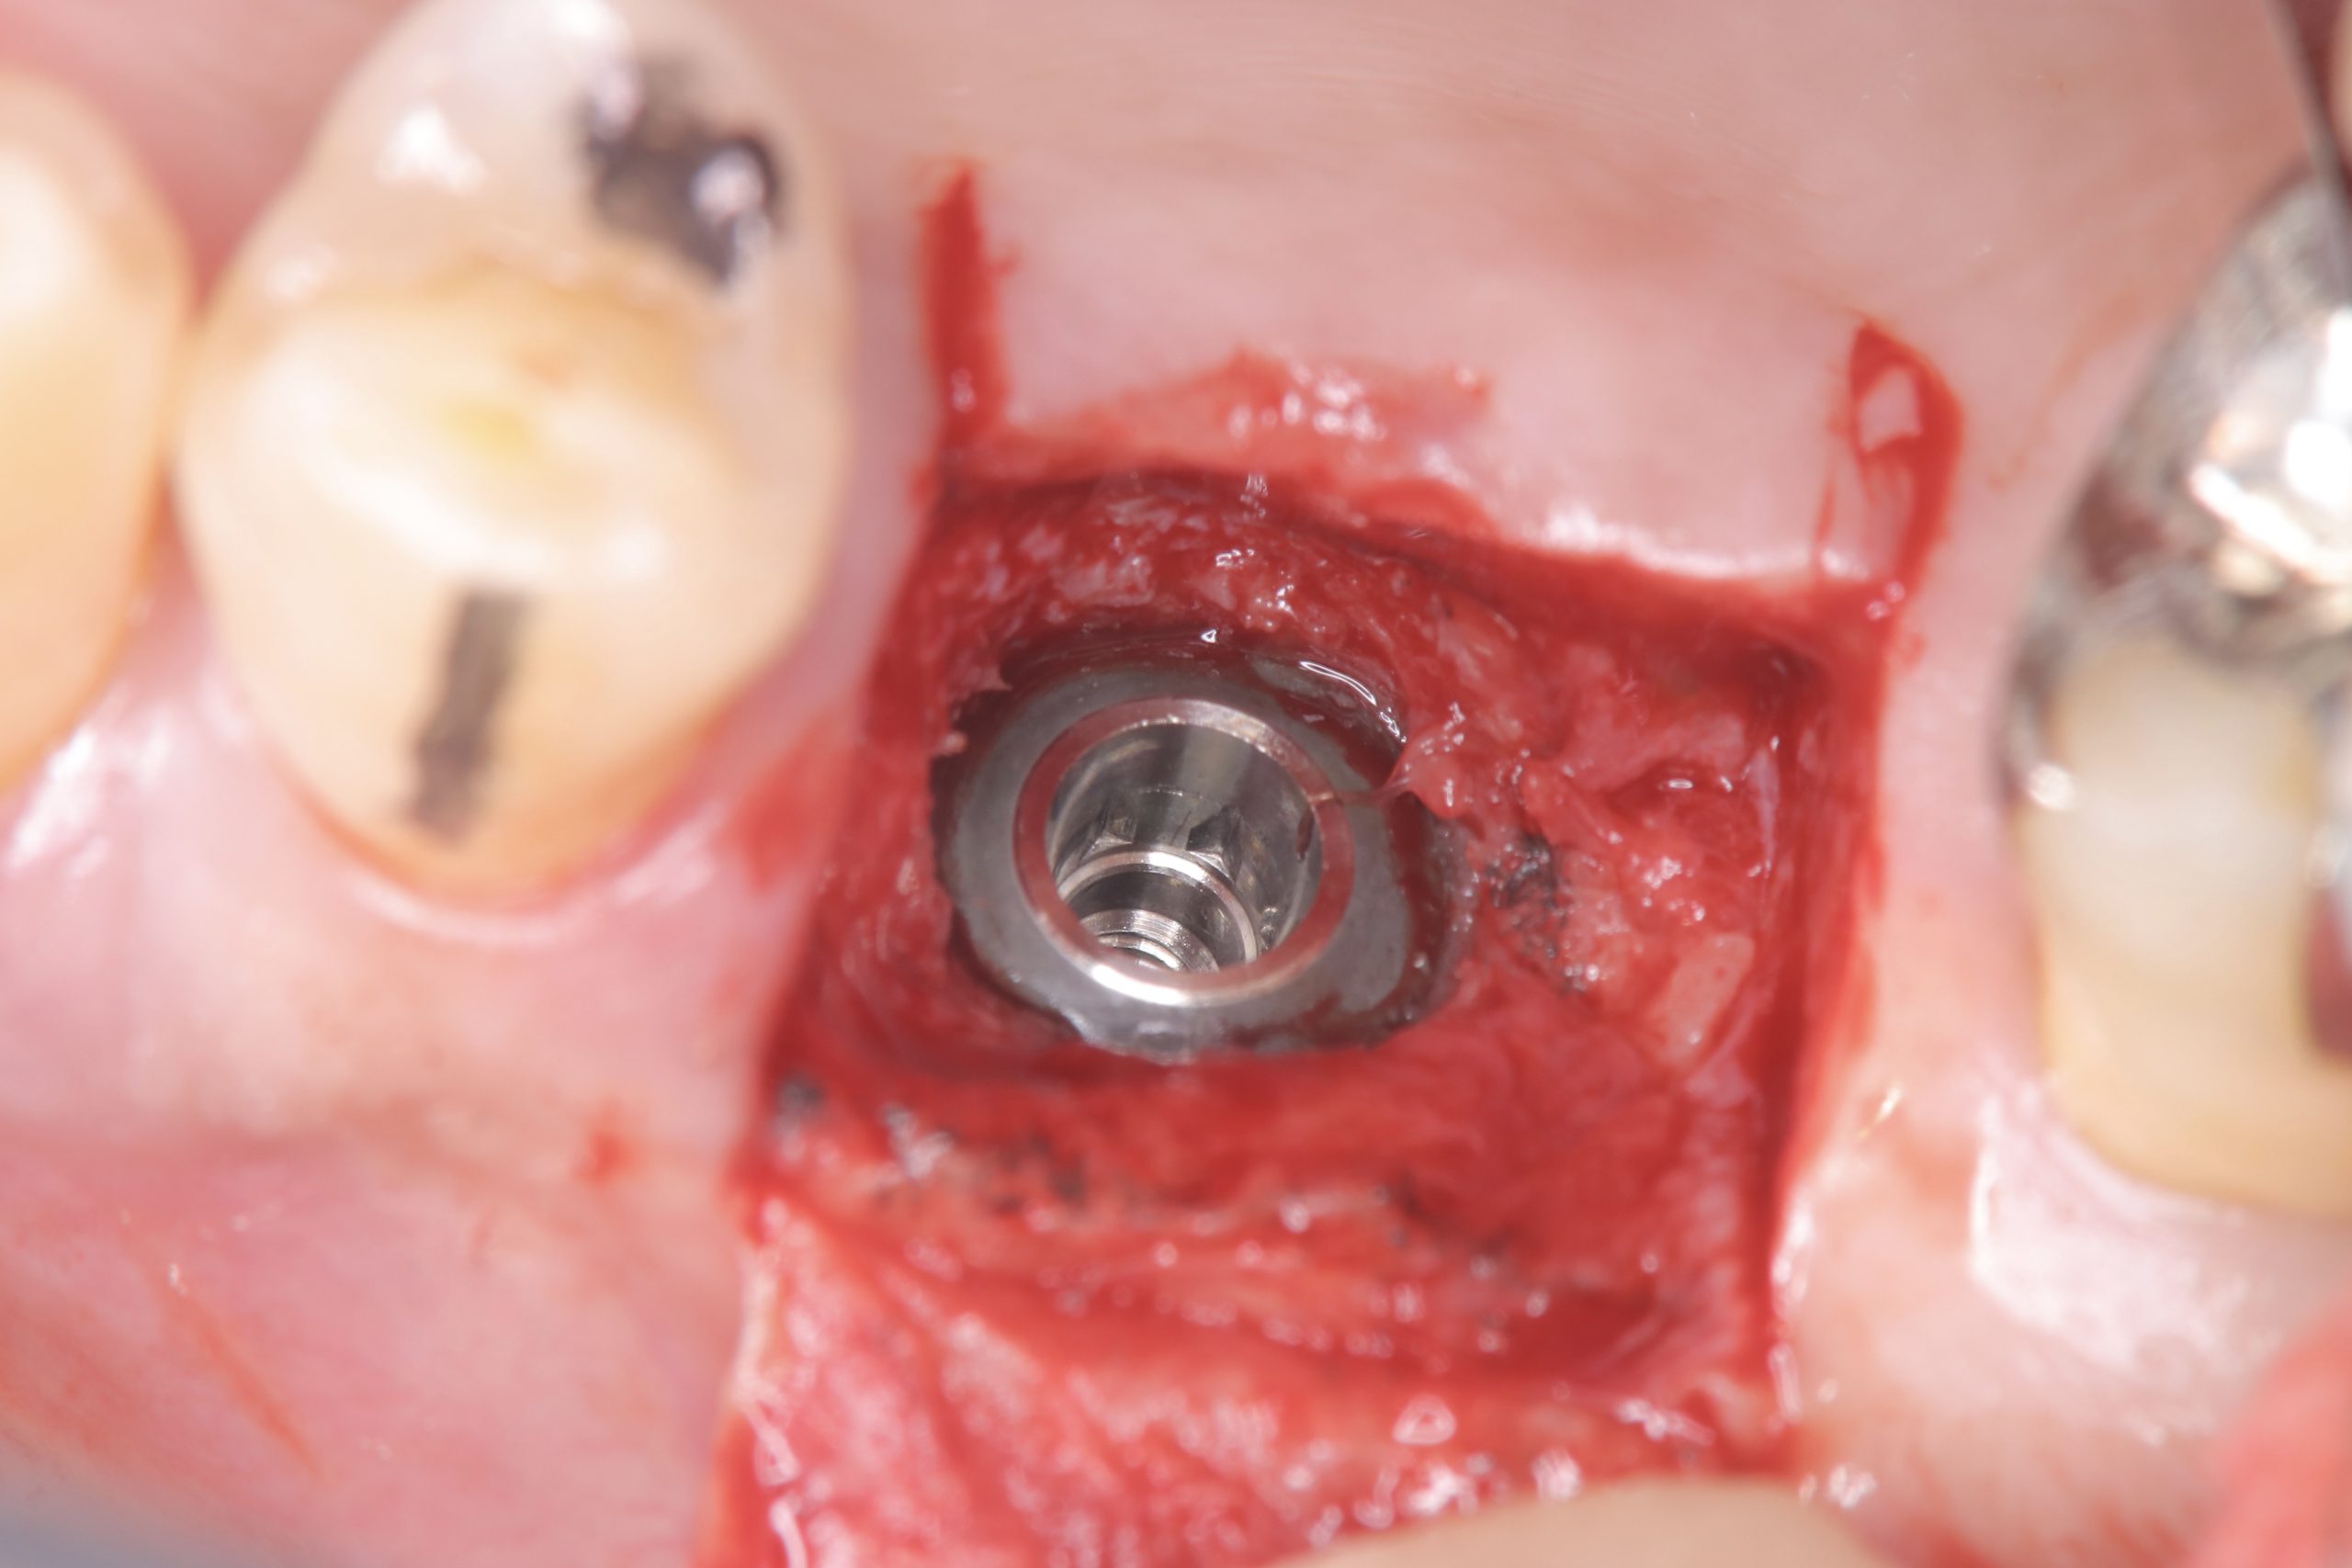

朝から、インプラントオペ

残存骨0.5から2ミリ内の難儀なリフティング

予想に反し、計測値も非常に良く😱

難なく30分で終わり💪